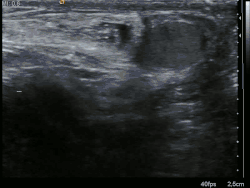

| Alça do intestino delgado (small bowel) que se projetou para o interior do saco escrotal, em direção ao testículo esquerdo. | |